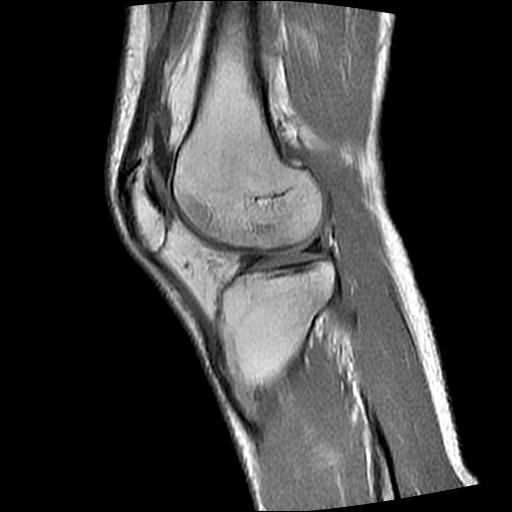

标题: MRI1265:男性40岁,右膝关节 [打印本页]

标题: MRI1265:男性40岁,右膝关节

40岁男性,右膝关节外伤,x光平片示,髁间隆突撕脱骨折。

1、前交叉韧带撕裂;

2、外侧半月板后角撕裂;

3、关节腔积液。

前交叉韧带撕裂,关节腔积液.

半月板1-2级损伤   前交叉韧带撕裂伤   关节腔少量积液  诸骨未见新鲜外伤性改变

髁间隆突撕脱骨折;内侧副韧带损伤。

内侧副韧带撕裂及关节腔积液是肯定的,但是前交叉撕裂确定吗?会不会有容积效应的因素,因为前一张前交叉显示清楚,连续性良好,且较光滑。请问楼主有关节镜支持吗?我们医院也经常有这样的患者,但苦于没有关节镜,而无法对照、证实(除非完全断裂),出现了不同的诊断结果只能毫无意义的争论。

1、前交叉韧、内侧副韧带撕裂;

3、关节腔积液。4、髁间脊撕脱骨折。

除了关节积液外并无韧带撕裂,acl胫侧附着点有2束,正常情况下脂肪信号。此病例应加做压脂像以便观察是否有骨损伤。